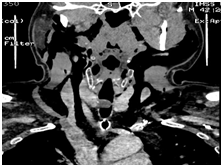

A 42-year-old male with a history of Diabetes mellitus type of 14 years of evolution, systemic arterial hypertension (ASH) of recent diagnosis that started 2 years ago, presenting dyspnea of medium effort, as well as dry cough and intermittent pharyngodynia. In December of 2013, a hemoptysis was added, so his hospitalization was decided and he was discharged on the third day. Bronchoscopy was performed by pulmonologist, finding a tumor between the 3rd and 4th tracheal ring, obstructing 80% of the lumen of which (Figure 1) a biopsy was taken, which was reported as cystic adenoid carcinoma with a cribiform and tubular pattern. They requested our assessment to perform a low tracheotomy we request assessment by performing a low tracheostomy. CT Computed tomography of the neck is requested, observing at the level of the first tracheal rings rounded lesion, attached to the wall which measures 13x13x1mm, being limited to the tracheal light occupying 85% of the same, without data of infiltration of adjacent tissues with important enhancement when applying contrast medium (Figure 2) (Figure 3). Evaluated by surgical oncology in March 2014 and May 2014 to perform neck exploration and resection of the 1st to 3rd tracheal ring with tracheal plasty, finding tumors from the 1st to the 3rd tracheal ring with free edges according to the transoperative examination, 4 days in the ICU with adequate evolution without need of ventilatory support, without presenting data of respiratory difficulty, with adequate evolution, it is discharged without the need of additional treatment. I do not consider it necessary to administer chemo-radiotherapy, the last tomographic control in November 2014 without evidence of tumoral activity, asymptomatic.

Figure 1 Tracheal mass seen by endoscopy.